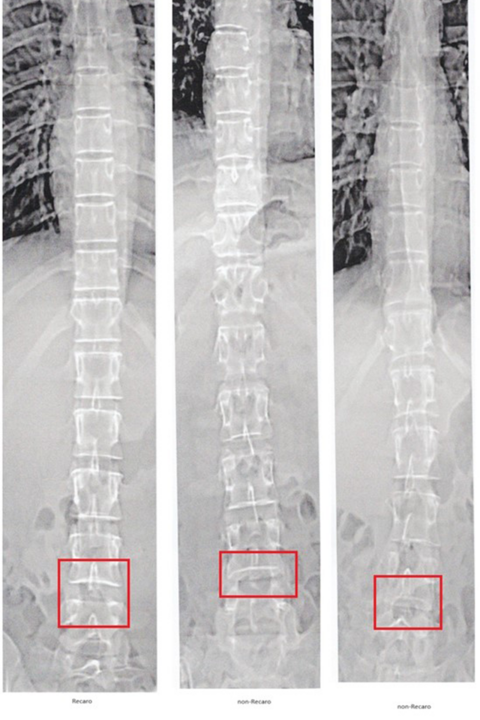

Laboratory Assessment: Five female drivers participated in the laboratory phase at Michigan State University. Their spinal columns were scanned using Dual Energy X-Ray Absorptiometry (DXA) to measure the distance between lumbar vertebrae. The participants were categorized based on whether they used a RECARO or non-RECARO seat. The hypothesis was that the RECARO seat, designed for female racers, would result in less spinal movement and reduced disk compression, potentially preventing long-term back injuries.

Lumbar Vertebrae: Preliminary data suggested that non-RECARO seats might contribute to a reduced gap between lumbar vertebrae, indicating potential spinal compression during impacts. Although the sample size was small, these findings align with anecdotal evidence from female racers.